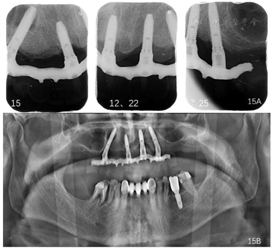

随访及转归:上颌种植固定义齿修复5年,每年定期复查,修复体完整稳固,无机械并发症发生;种植体周围软组织健康稳定(图11A~I,图12A~I,图14)。

随访X线检查示4颗种植体周围骨结合良好(图10,图11J,图12J,图13,图15)。

该病例双侧上颌窦腔形态不对称,右侧上颌窦外侧壁前缘位于侧切牙区,其与底壁的连接区接近右侧尖牙的根尖区,在种植体通过的区域存在上颌窦间隔,按照Jensen[12]的All-on-4®种植修复设计方案分类,常规种植体长度的斜行种植不能正常实现。Malo等[13]曾报道多例在后牙区因重度牙槽骨萎缩,采用All-on-4®术式斜行植入植体时,通过直接穿上颌窦,实现了牙槽嵴顶及鼻底皮质骨固位,在避免上颌窦底提升术的同时,完成了即刻种植即刻负重并获得了3年稳定的治疗效果。本例患者在斜行植体穿上颌窦时,附加了外侧壁开窗剥离上颌窦底黏膜,手术直视下使种植体通过上颌窦间隔,并保证了上颌窦黏膜的完整性,种植体尖端达鼻底,利用牙槽嵴顶及鼻底双层皮质骨固定,满足种植体初期稳定性的需求。术中未使用骨移植材料,仅使用了浓缩生长因子覆盖于植体周围,研究表明[14]浓缩生长因子可明显减轻术后肿胀程度,缩短肿胀时间,且富含血小板、多种生长因子,能够促进软组织生长[15、16]。这与Jensen[2]在2012年报道的穿上颌窦植骨All-on-4®即刻种植即刻负重的案例不同。文献报道穿上颌窦All-on-4®即刻种植即刻负重的案例中,植骨和不植骨的患者,在1年负重之后的植体失败率、并发症发生率及植体周骨吸收程度并无显著统计学差异[17]。本例采用穿上颌窦不植骨All-on-4®即刻种植即刻负重,5年随访期内右侧上颌窦无临床不适症状,X光影像学检查未见异常,获得了良好的治疗效果。

随访维护期内发现患者右侧下颌第二前磨牙与第一磨牙牙周炎症较5年前进一步发展,影像学检查示牙槽骨吸收至根尖(图15),符合拔牙指征[7,8],患者知情同意后拔除,后期及时修复,保持全牙列的咬合平衡。